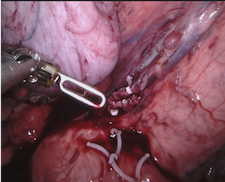

As robotic minimally invasive surgery has developed, with platforms such as da Vinci becoming the de-facto standard-of-care for certain urological, gynecological and general surgical procedures, there has been an increase in focus in how assistive systems based on computer vision and machine learning can improve surgeon performance and patient outcomes. Many potential applications are dependent on scene understanding and for this, accurate segmentation of instruments is an important component. For instance, instrument tracking algorithms which underlie automation and guidance assistance often build upon segmentation [4] or alternatively masking augmented reality overlays of 3D imaging modalities requires pixel labelling of the instruments to prevent their occlusion (see Fig. 1).

Our challenge was made up of 3 sub-problems. The first was binary instrument segmentation, where each frame was separated into da Vinci Xi instruments and a background class, which contained an ultrasound probe, surgical clips and porcine tissues. The second task was instrument part segmentation, where we scored the participants on whether they could correctly segment each articulating part of the instrument (see Fig. 3). Our final task was to segment and classify the instruments (see Fig. 4).